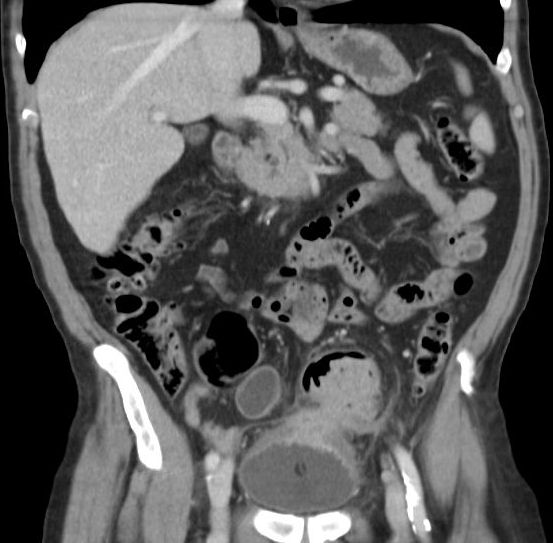

| Ileus | 78-jährige Frau in der Notaufnahme wegen Ileus. Tumor am deszendo-sigmoidalen Übergang. Hemokolektomie: Ulzeriertes Adenokarzinom pT3b pN1a (1/12)Mo L1 Vo. | ||

![]() |

![]() | |

| Ileus | Das CT zeigt einen stenosierenden Sigmatumor mit ausgeprägtem Ileus. |